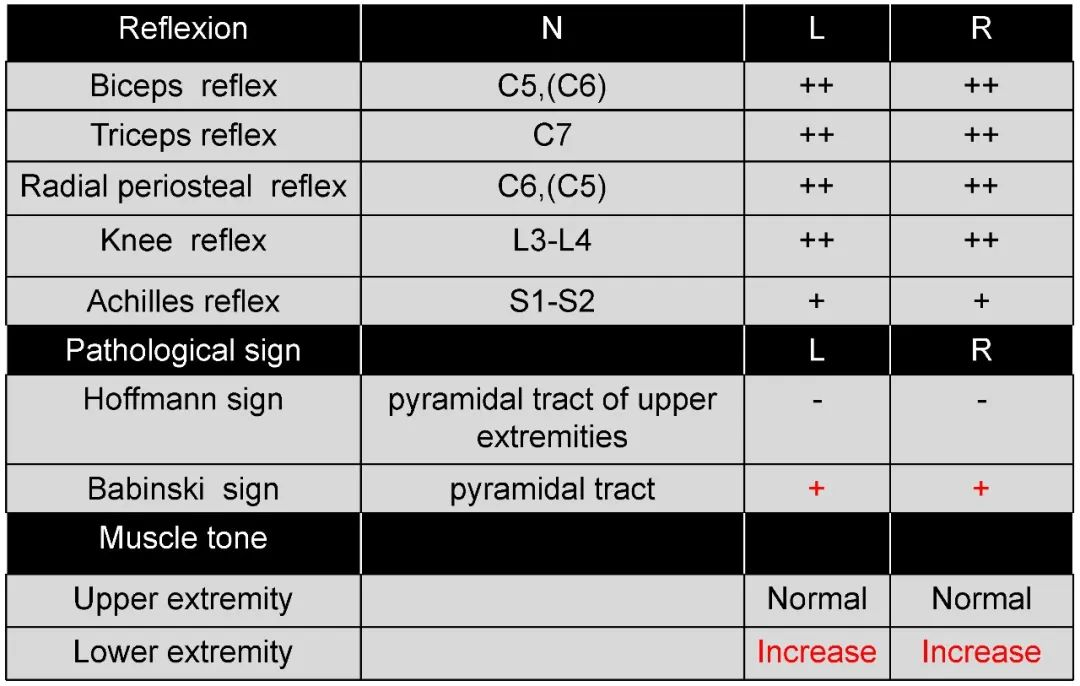

病史:M, 34 y/o

Numbness of right lower limb for 2 months, weakness for 1 week

Urination disorder

Body Weight: 120Kg; BMI: 39.5

Thoracic spinal stenosis(T2-T3)

Thoracic spinal stenosis decompression(T2-T3)

术后3个月: